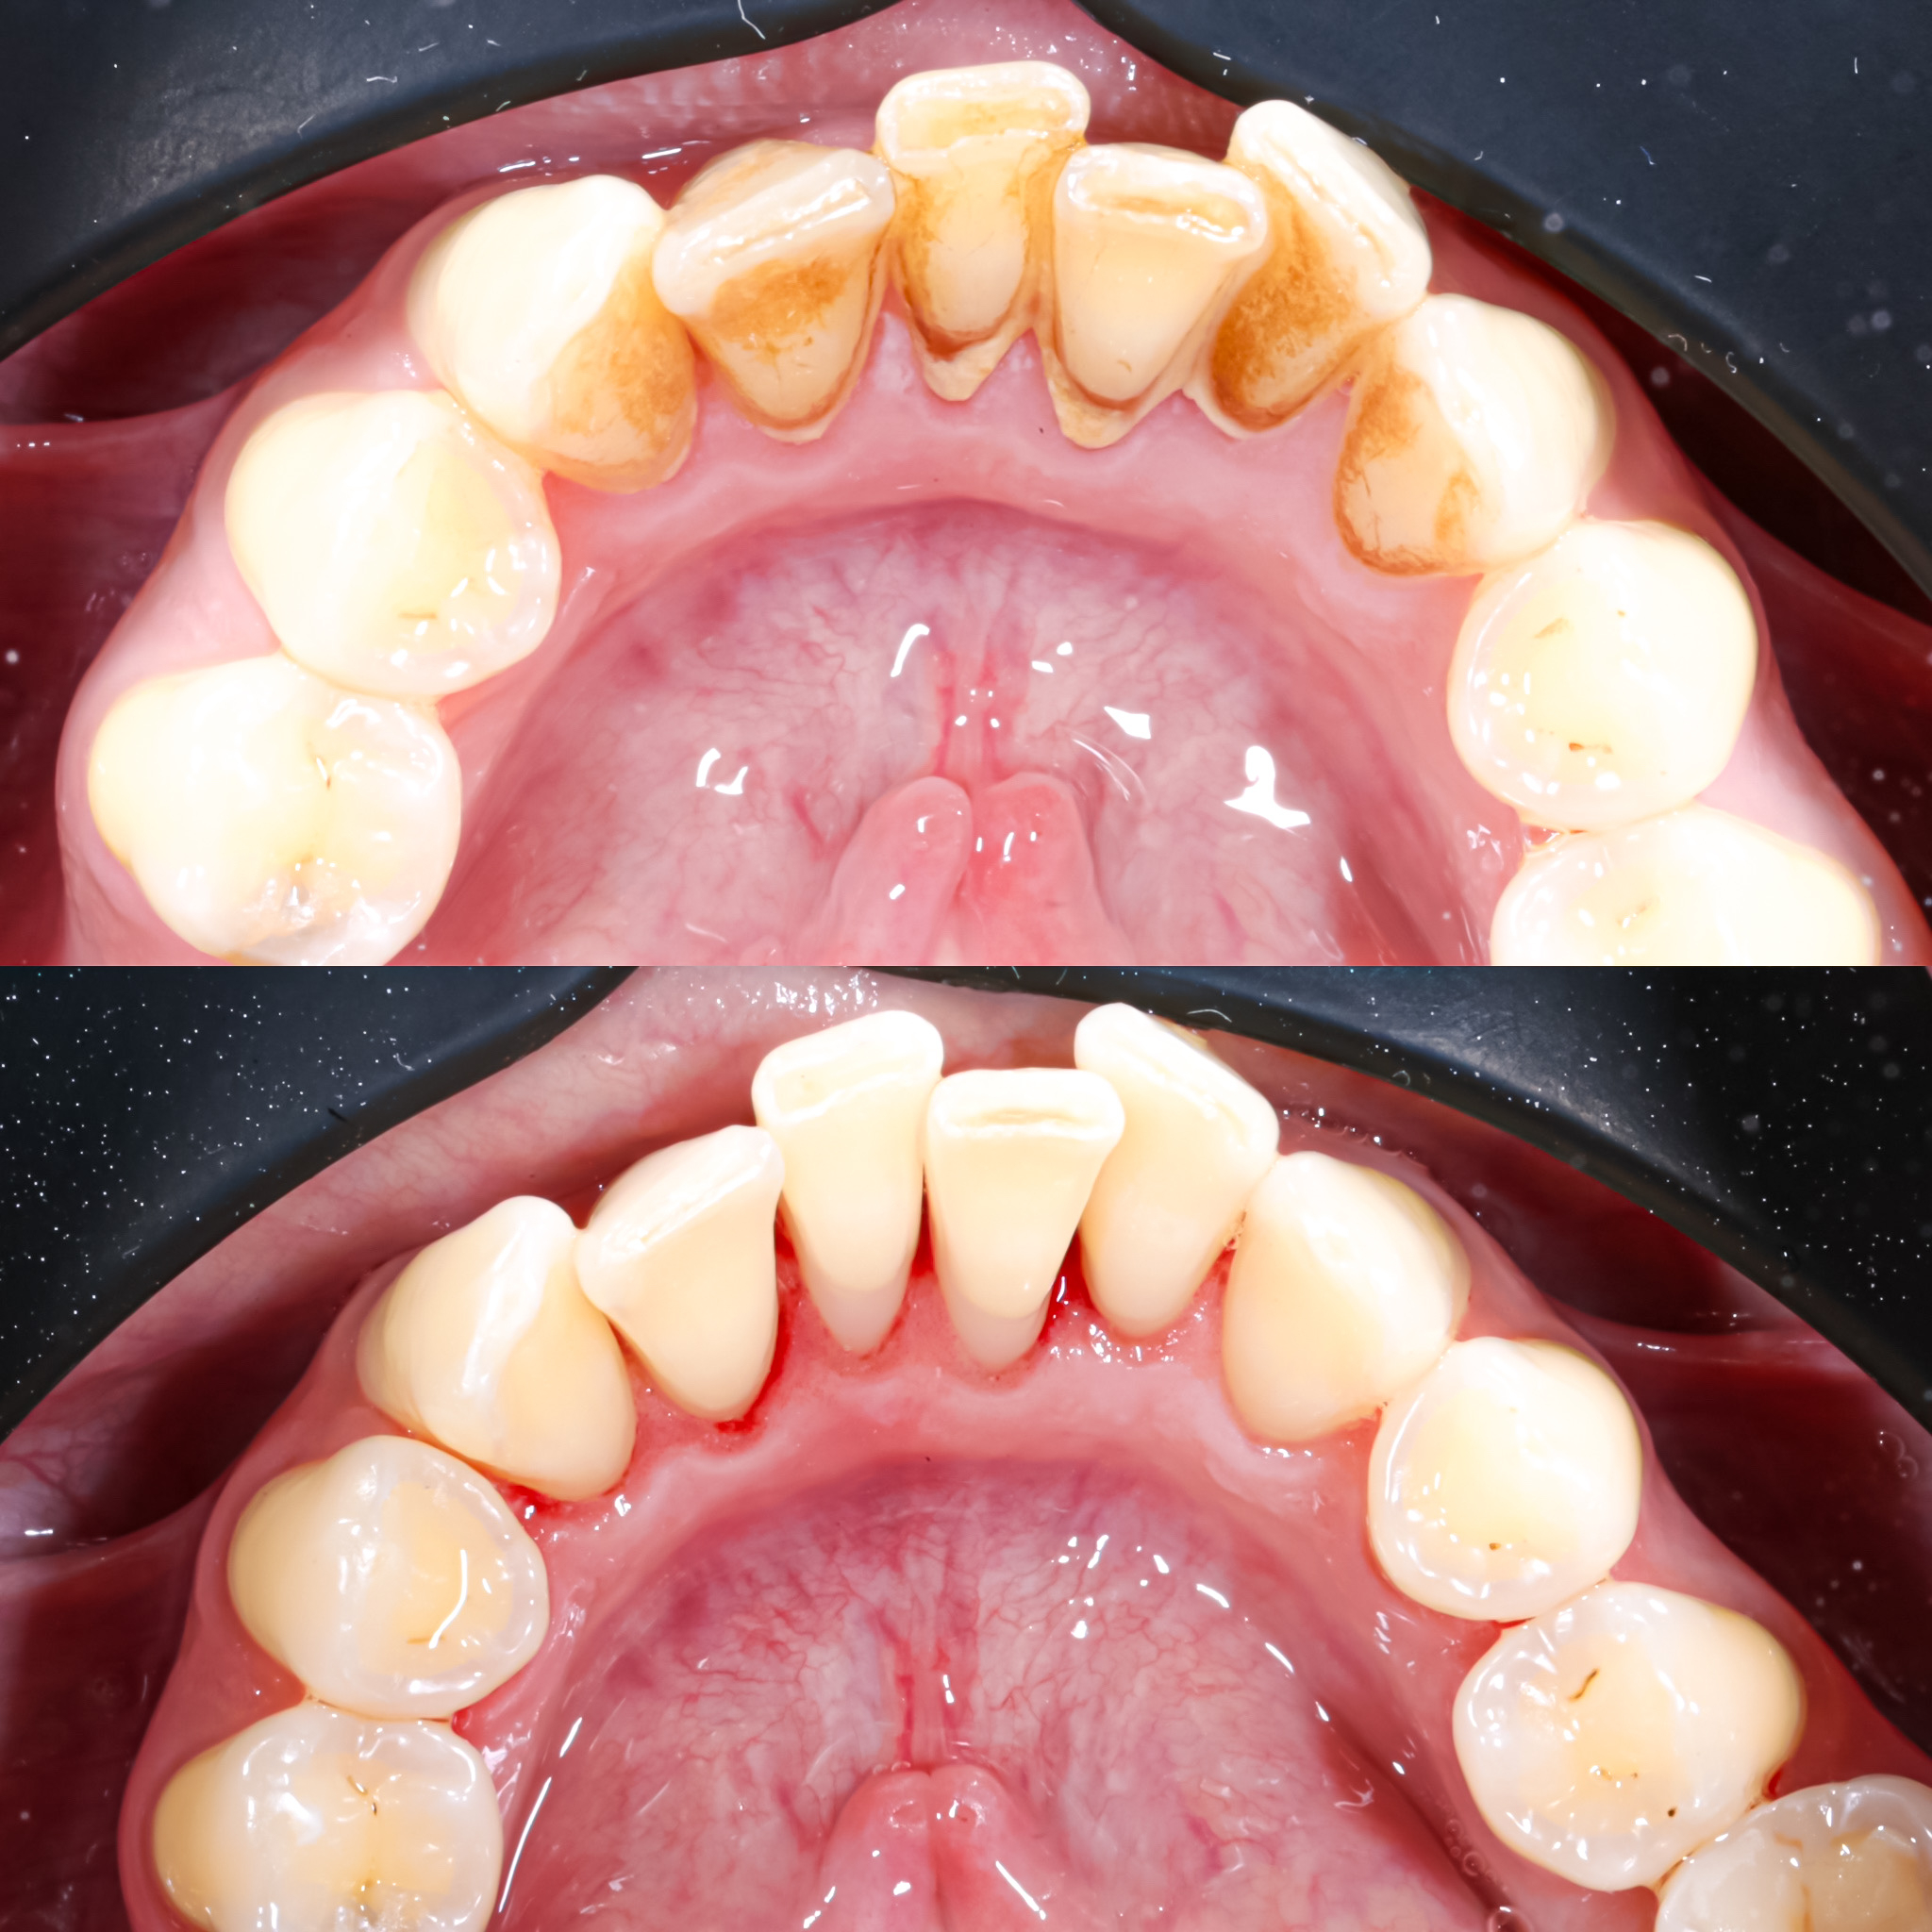

Галерея

Професійна гігієна (чистка) зубів складається з кількох етапів

Повітряно-абразивна чистка зубів (Air Flow)

Завдяки піскоструменевому апарату з технологією Air Flow, який використовуючи тиск повітря та води, подає на зубну емаль спеціальний абразивний склад, зуби можна очистити не лише від м’якого нальоту, а й від пігменту. Для видалення нальоту, в Космічній стоматології Драганчука ми використовуємо KaVo prophy pearls supragingival calcium carbonateneutral.

Чистка зубів щіточками та пастами

Фінальний етап професійної гігієни - полірування спеціальними щіточками та пастою, щоб усунути мікротріщини та шорохуватості, що виникли після чистки та видалити залишки нальоту, що могли в них залишитись. Це дозволяє суттєво уповільнити формування нових відкладень.

Полірування зубної емалі гумками

Кінцеве полірування поверхні зубів проводиться із застосуванням різних насадок, зокрема спеціальних гумок, що надає зубам ідеальної гладкості та блиску. Спеціальні гумові насадки відмінно справляться з наданням естетичної довершеності твоїй посмішці.